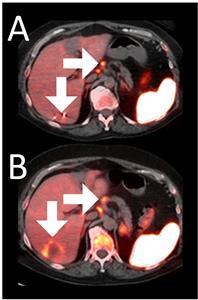

Example 3: Patient 15-006:

A 64-year-old woman with ER+/PR-/HER2- metastatic breast cancer, heavily pre-treated with 8 prior lines of therapy, including the antibody-drug conjugate Trodelvy, remains alive 25 months post-enrollment. At baseline, presented with hepatic metastasis.

Before BriaCell Treatment Image A: A liver metastasis (lower arrow) is “cold,” indicating minimal to no CD8+ cytotoxic T cells in the tumor while enlarged lymph nodes (upper arrow) show moderate uptake.

After BriaCell Treatment Image B: Swelling (induration) around the metastasis (lower arrow) demonstrates the liver metastasis has become “hot”, indicating marked CD8+ cytotoxic T cell infiltration while further lymph node enlargement is consistent with increased activity (upper arrow) indicating increased CD8+ T cells.

Example 3 Images (Patient 15-006): Combined MRI and CD8 ImmunoPET images Pre (A) and Post (B) Bria-IMT treatment

Example 3 Images (Patient 15-006)

Combined MRI and CD8 ImmunoPET images Pre (A) and Post (B) Bria-IMT treatment